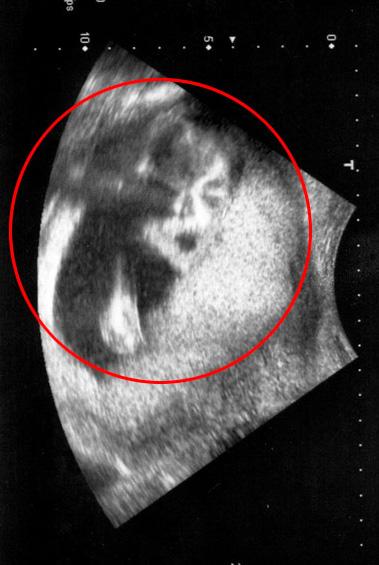

孕婦道恩·凱莉的B超照片上竟出現(xiàn)邁克爾·杰克遜的影像

據(jù)英國《太陽報(bào)》11月19日報(bào)道,近日,即將為人父母的一對英國夫婦在前往醫(yī)院對胎兒進(jìn)行B超檢查時(shí),竟然驚奇地發(fā)現(xiàn),照片上出現(xiàn)了一張已故歌王邁克爾·杰克遜的臉!

這一次,她被送往臨近的格林頓·雷恩便利中心進(jìn)行更仔細(xì)的檢查。但是當(dāng)掃描結(jié)果出來后,夫婦兩人被驚得目瞪口呆,片子上已故歌王邁克爾·杰克遜正兩眼直勾勾地“盯著”他們!

29歲的擦玻璃工人威廉姆也證實(shí)說:“我們又仔細(xì)地看了一遍片子,但還是只看到了邁克爾·杰克遜。”孕婦道恩說,“一開始我還以為是自己看花眼了,所有還把片子拿給我6歲的女兒艾米看,她也一眼就發(fā)現(xiàn)了不正常的現(xiàn)象!

如今,道恩已經(jīng)懷孕24周了,預(yù)計(jì)將于明年3月生產(chǎn)。她說:“我以前做過很多次B超檢查,但沒有一次出現(xiàn)過這樣的情況,這簡直太詭異了!”這對夫婦還表示,不打算給自己即將出生的孩子起名為邁克爾,因?yàn)闄z查結(jié)果已經(jīng)明確顯示這是一個(gè)女孩。(Zak)